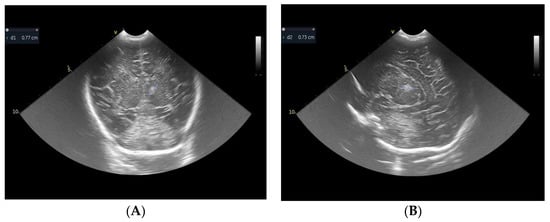

2. Case Report